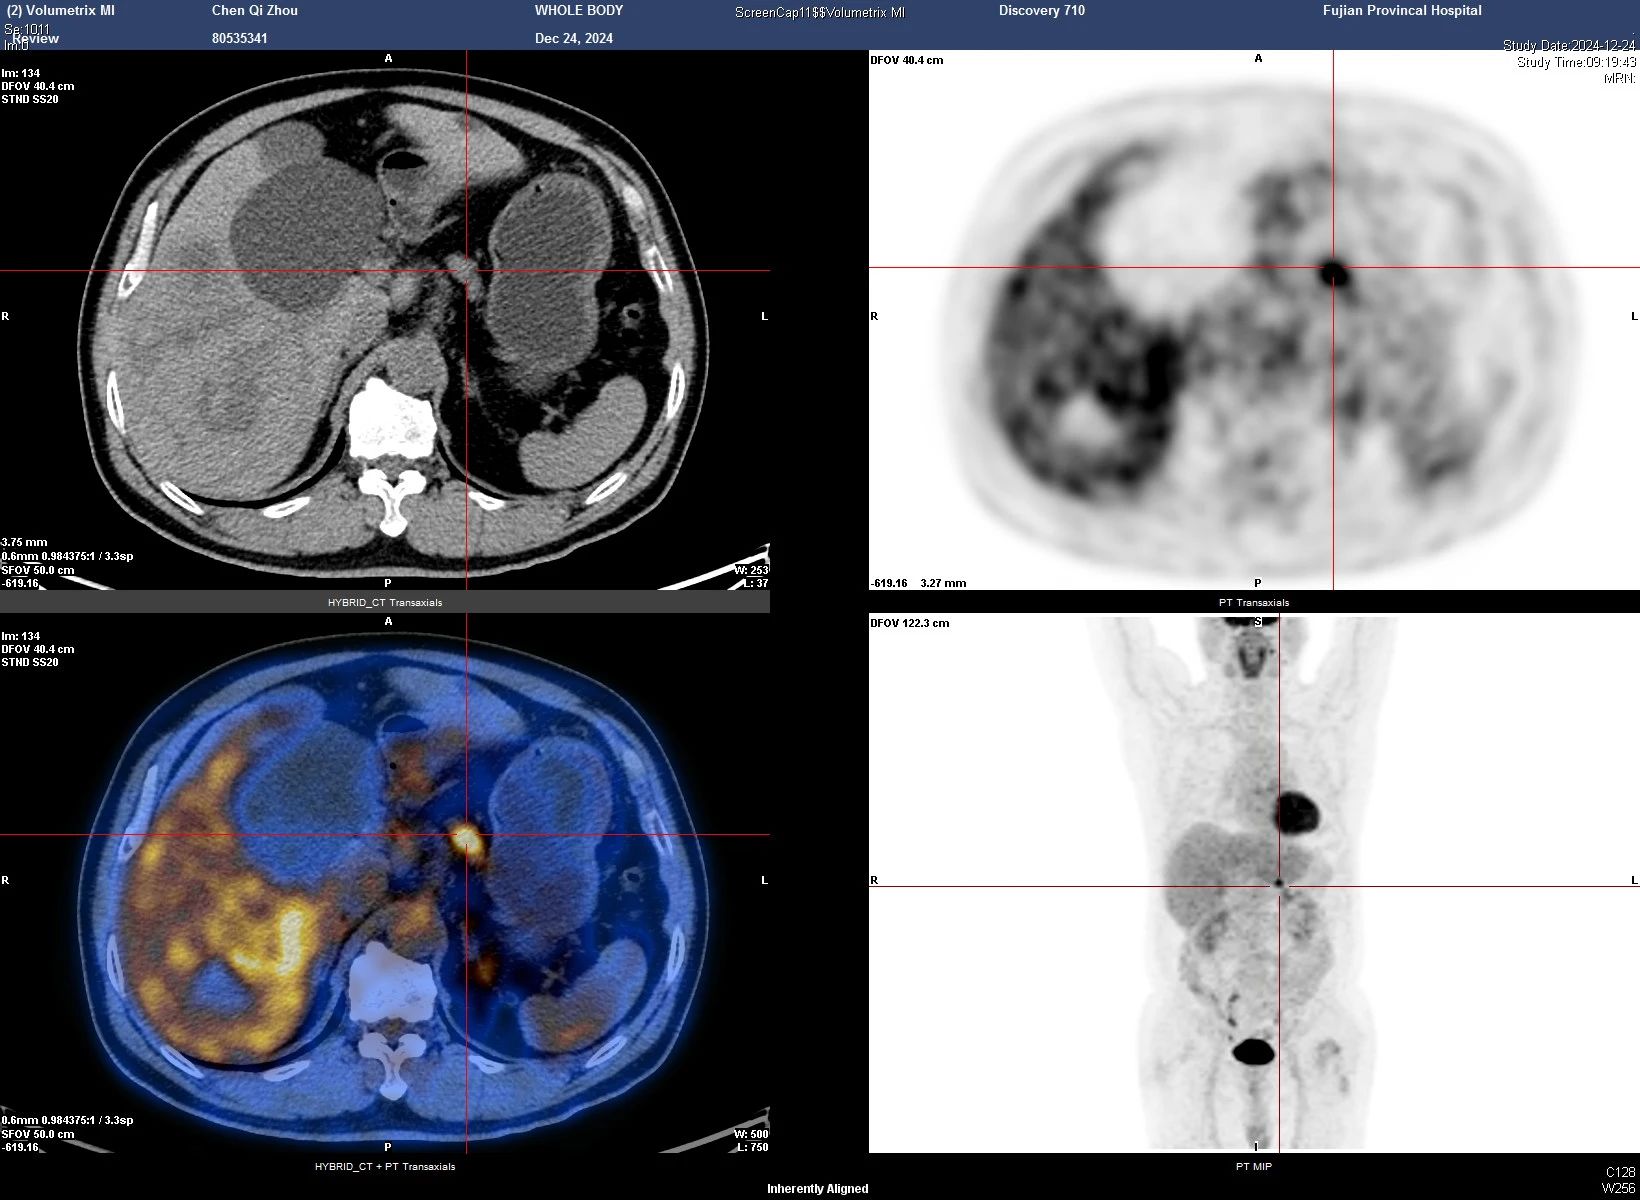

祸不单行,陈老师的术前检查还提示胰腺体部存在 2.5×1.5cm的占位。得益于我院先进的磁共振和PET-CT 检查,精准为外科手术提供了重要依据。这处占位可疑来源于肝癌的转移病灶,肝癌转移到胰腺的情况在临床上非常罕见,文献报道仅占2.7-5.6%。

图示胰腺转移灶